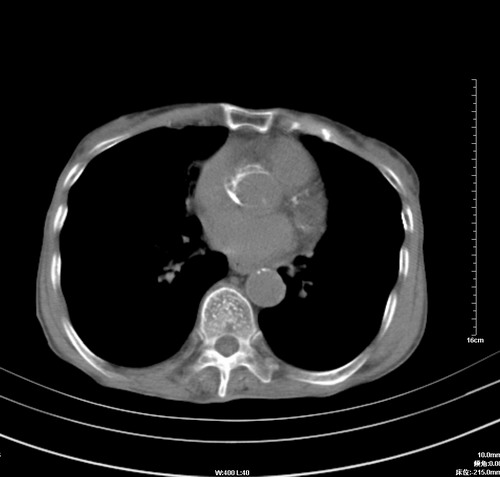

中后纵隔占位,气管、食道受压、变形、移位。恶性可能性大。

考虑:中后纵隔转移瘤可能性大,主动脉硬化。

1 气管旁、隆突下淋巴结明显肿大,肝左叶外侧段低密影,都考虑转移。

纵隔淋巴结肿大,考虑转移而来

肺癌,纵隔淋巴结转移,肝左叶病变考虑为转移病灶。

中后纵隔转移瘤可能性大,主动脉硬化。

后中纵隔团块影,伴气管、食道受压移位,首先考虑转移瘤,肝s5段低密度灶。建议增强检查,另外其结肠是否有问题请提供,右肺部分肺叶局限含气增多,考虑局限肺气肿。

建议强化检查,考虑纵隔型肺癌,小细胞可能性大。

后中纵隔淋巴结肿大,首先考虑转移瘤。